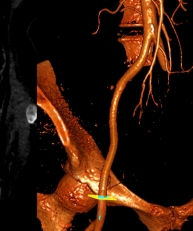

主动脉CT

原生物瓣形态:最大直径18.3mm;

冠脉风险尚可;冠脉切线面窦宽30mm,冠脉距离生物瓣距离>4mm,风险可控;

入路情况:升主有扩张,直径46mm,胸主腹主动脉无明显迂曲,双侧股动脉入路较好,右股可作为主入路;

考虑植入深度:生物瓣缝合环下5mm。